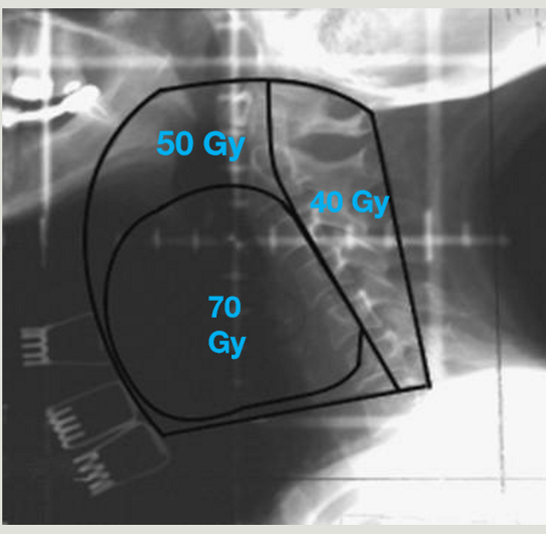

RT glottis set-up

supine on AIO board, 4-point shell, arms by sides with knee and ankle rests

RT glottis

energy

technique

collimator angle

D/F accelerated conccurent boost

D/F Post-op

6 MV

lat POP with fields centered on vocal cords (5×5 fs)

angle follows vertebral bodies

70 Gy / 35 fraction

64-60 Gy / 27-30 fraction

what are the sup, inf, ant, and post RT borders for glottic cancer

sup = thyroid notch or hyoid bone

inf = border of cricoid cartilage (c6)

ant = clear skin 1-1.5 cm at level of vocal cords (FLASH) + 1 cm bolus for nodal treatment

post = between ant edge and middle of vertebral body, including anterior portion of pharyngeal wall